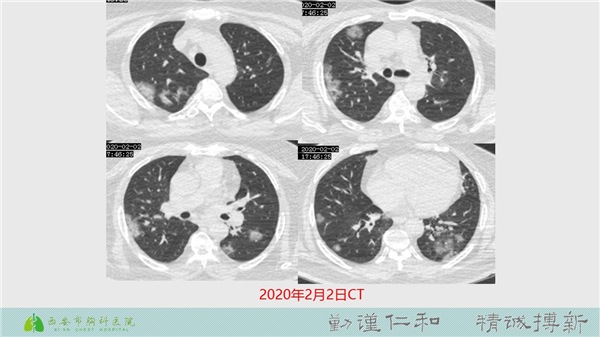

【病例分享】新型冠狀病毒肺炎4例(西安市胸科醫(yī)院)